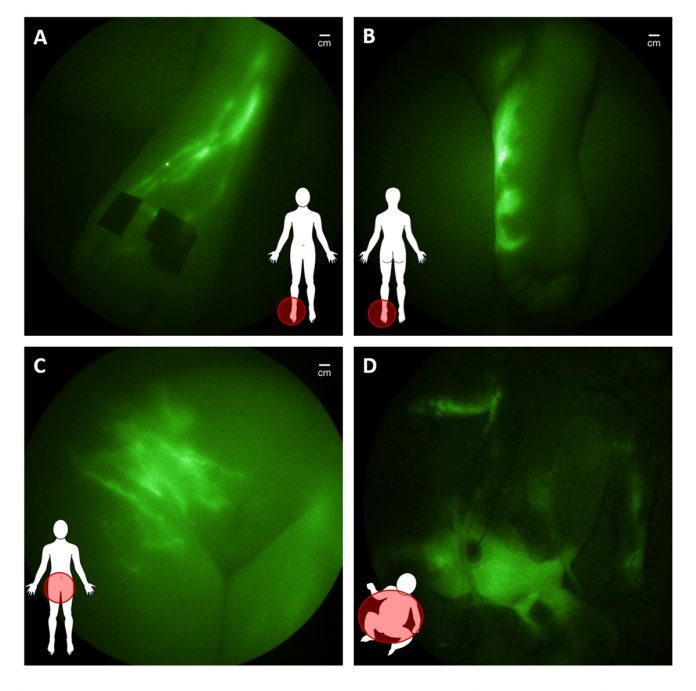

In translational studies funded in part by the National Institutes of Health and conducted under investigational new drug applications from the FDA, we have used the NIRF technology to dynamically image the lymphatics of over 400 subjects, including 30 infants and children. The imaging begins with an intradermal injection of 0.05- 0.1 mL of saline containing microgram amounts of ICG into the region of interest. ICG administration on the top of the foot results in immediate uptake into the main conducting vessels (Figure 2A) that proximally “pumps” ICG-laden lymph into the inguinal nodes before entering the central lymph channel that collects mesenteric and peripherally generated lymph for its return to the hemovascular system.

In children and adults with suspected lymphatic dysfunction, we have observed abnormal lymph drainage to the bottom of feet (Figure 2B), as well as pelvic, lymphatic congestion which in adolescents and young adults is associated with lower extremity lymphedema (Figure 2C) and, in some infants, with surgery-induced chylothorax (Figure 2D).